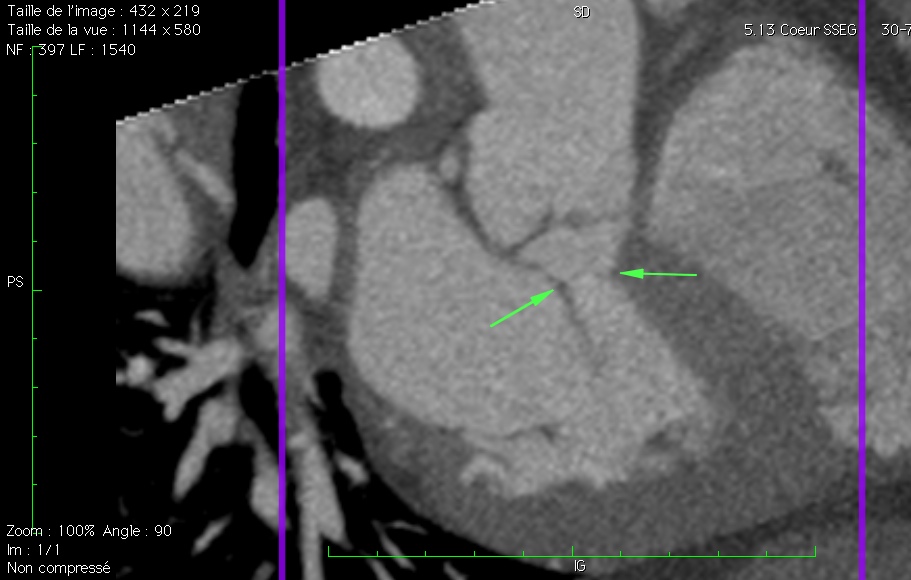

En scanner, la flèche du haut indique l’insertion septale du cordage :